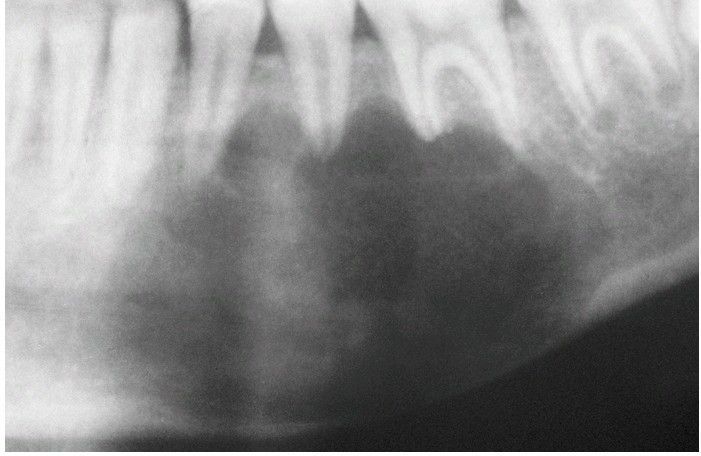

Panoramic film showing a large simple bone cyst of the mandible in a 12-year-old girl. The scalloping superior aspect of the cyst between the roots of the teeth is highly suggestive of, but not diagnostic for, a simple bone cyst.